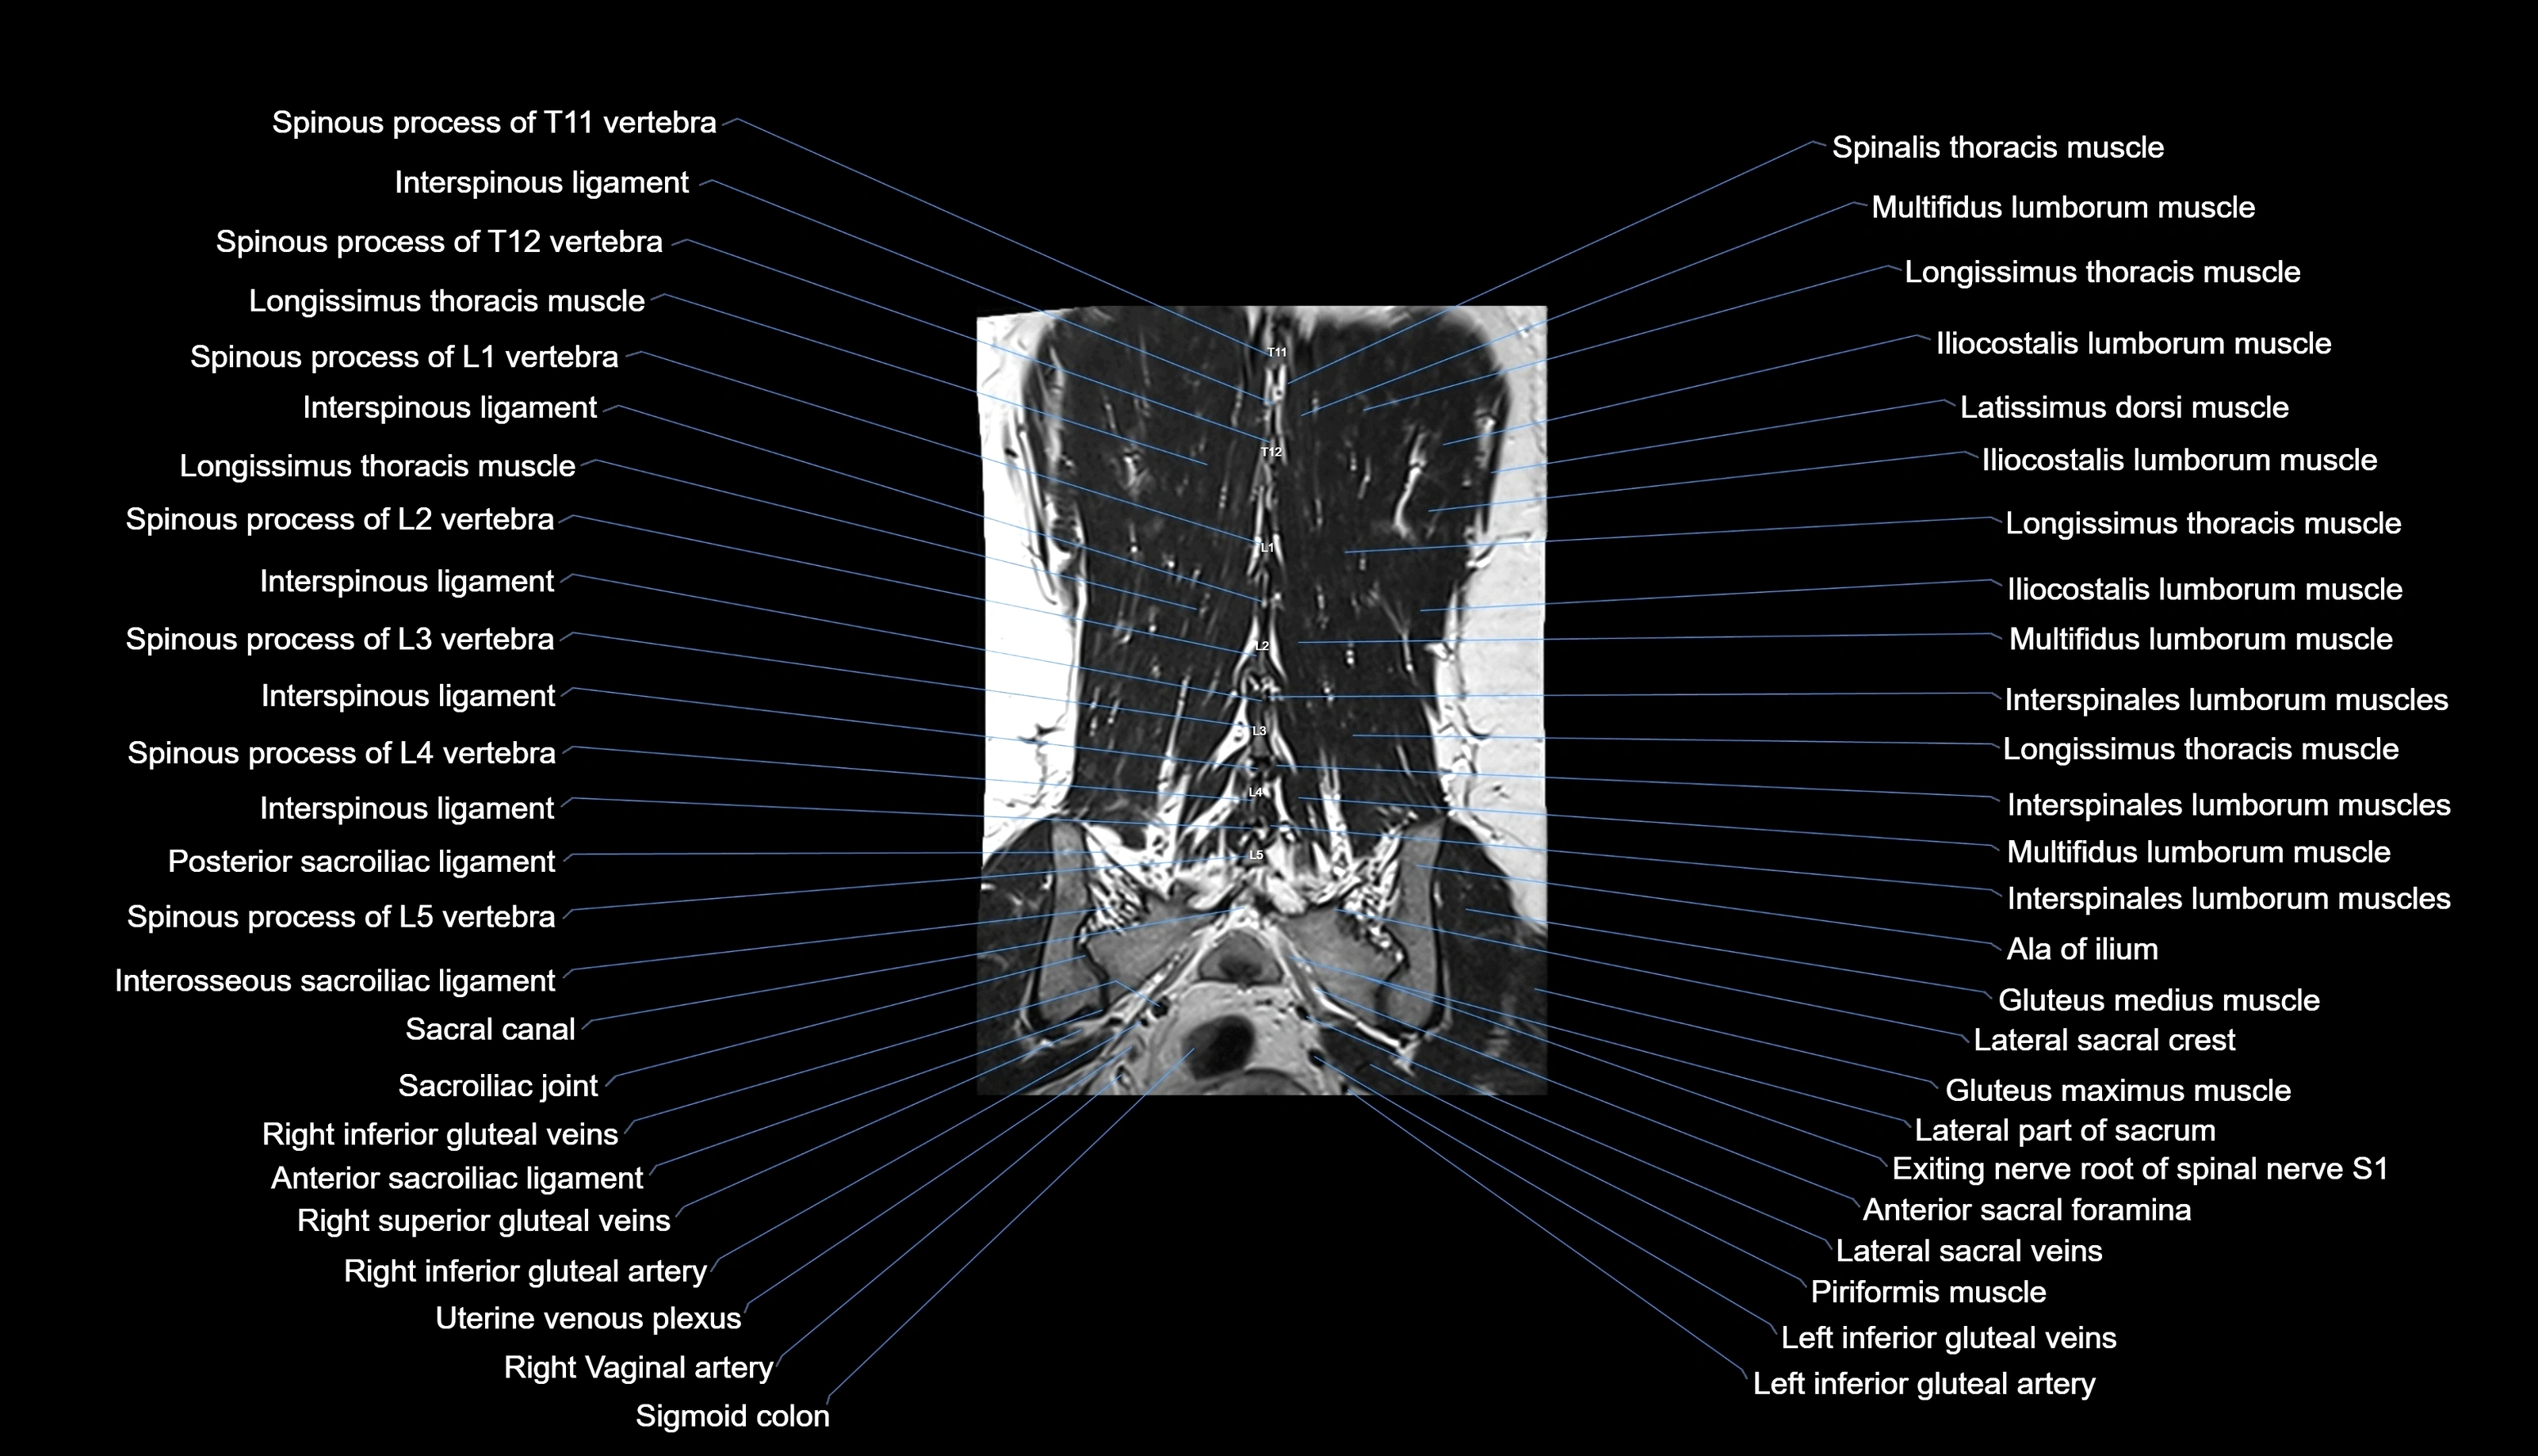

MRI images